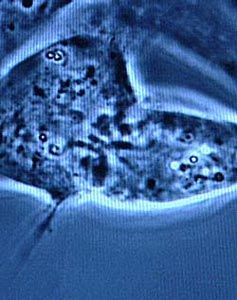

再生障礙性貧血診斷(二)骨髓象 急性型呈多部位增生減低或重度減低,三系造血細胞明顯減少,尤其是巨核細胞和幼紅細胞;非造血細胞增多,尤為淋巴細胞增多。慢性型不同部位穿刺所得骨髓象很不一致,可從增生不良到增生象,但至少要有一個部位增生不良;如增生良好,晚幼紅細胞(炭核)比例常增多,其核不規則分葉狀,呈現脫核障礙,但巨核細胞明顯減少。骨髓塗片肉眼觀察油滴增多,骨髓小粒鏡檢非造血細胞和脂肪細胞增多,一般在60%以上。

(三)骨髓活組織檢查和放射性核素骨髓掃描由於骨髓塗片易受周圍血液稀釋的影響,有時一、二次塗片檢查是難以正確反映造血情況,而骨髓活組織檢查對估計增生情況優於塗片,可提高診斷正確性。硫化99m鎝或氯化111銦全身骨髓γ照相可反映全身功能性骨髓的分布,再障時在正常骨髓部位的放射性攝取低下甚至消失,因此可以間接反映造血組織減少的程度和部位。